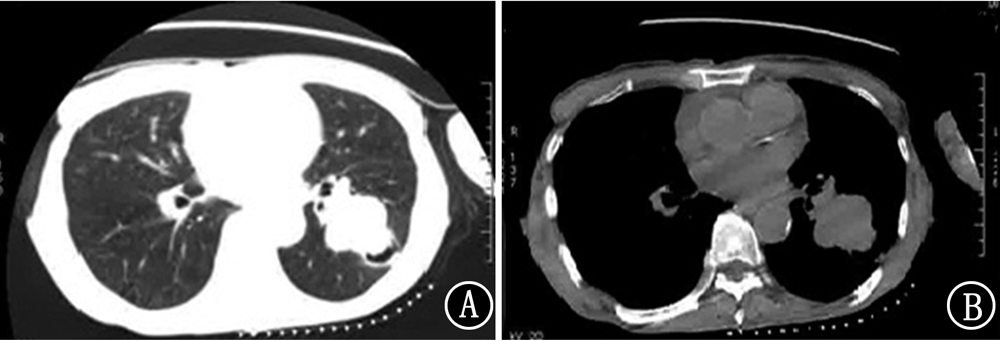

纳武单抗在肺鳞状细胞癌治疗中已广泛应用,但目前对药物引起的不良反应和处理了解有限。现报道1例纳武单抗治疗老年肺鳞状细胞癌的临床诊治经过,以此提高对该疾病治疗的相关认识。